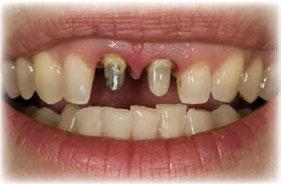

Para ilustrar el proceso, presentamos el caso de una mujer joven diagnosticada de carcinoma adenoide quístico en la región posterior del hemipaladar izquierdo (Figuras 1 y 2). El procedimiento quirúrgico realizado fue una

maxilectomía parcial que incluyó las piezas 24-26 y desde el reborde alveolar hasta la base del cráneo (Figuras 3 y 4). En este caso, la órbita y el globo ocular pudieron ser preservados. La reconstrucción inmediata se realizó mediante un colgajo de músculo temporal homolateral (Figura 5) y el defecto de la fosa temporal fue cubierto mediante una malla de titanio. Posteriormente, la paciente recibió radioterapia (Figuras 6 y 7). 2 años más tarde se diseñó un IS con anclaje en el arbotante nasomaxilar, zona subnasal izquierda

Figura 1. Imagen preoperatoria de la paciente.

Figura 2. Carcinoma adenoide quístico en región posterior del hemimaxilar izquierdo.